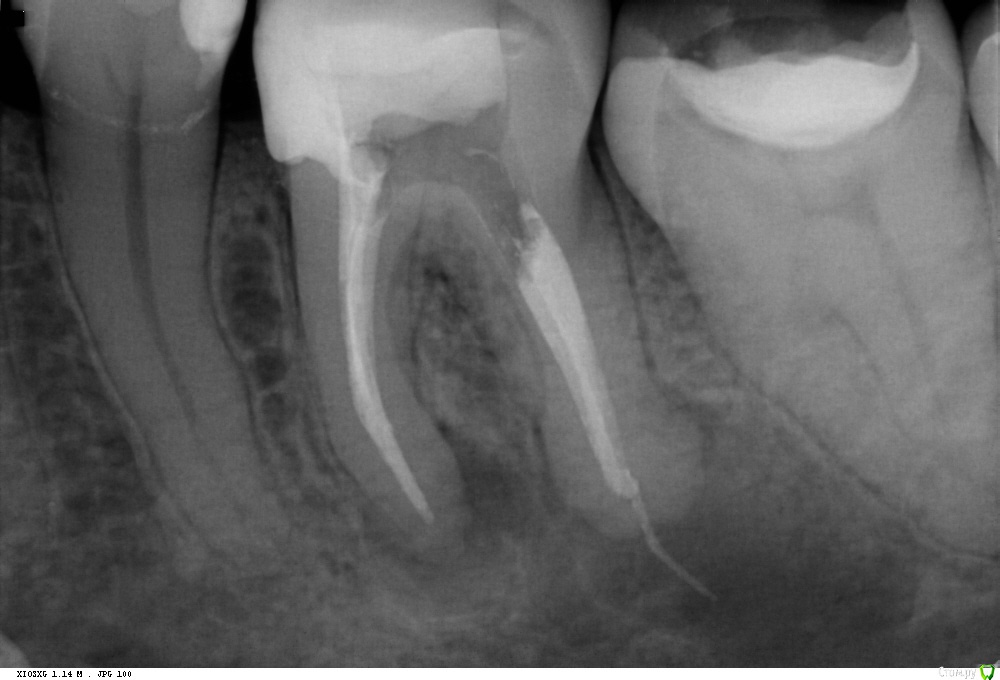

St. Опубликовано 30 января, 2018 Поделиться Опубликовано 30 января, 2018 До, с инструментом и после. Испортила немного картинку после выведенным силлером Ссылка на комментарий

St. Опубликовано 30 января, 2018 Поделиться Опубликовано 30 января, 2018 Сейчас после повторной распломбировки, апикальный размер больше, такое впечатление что идет активная резорбция там Ссылка на комментарий